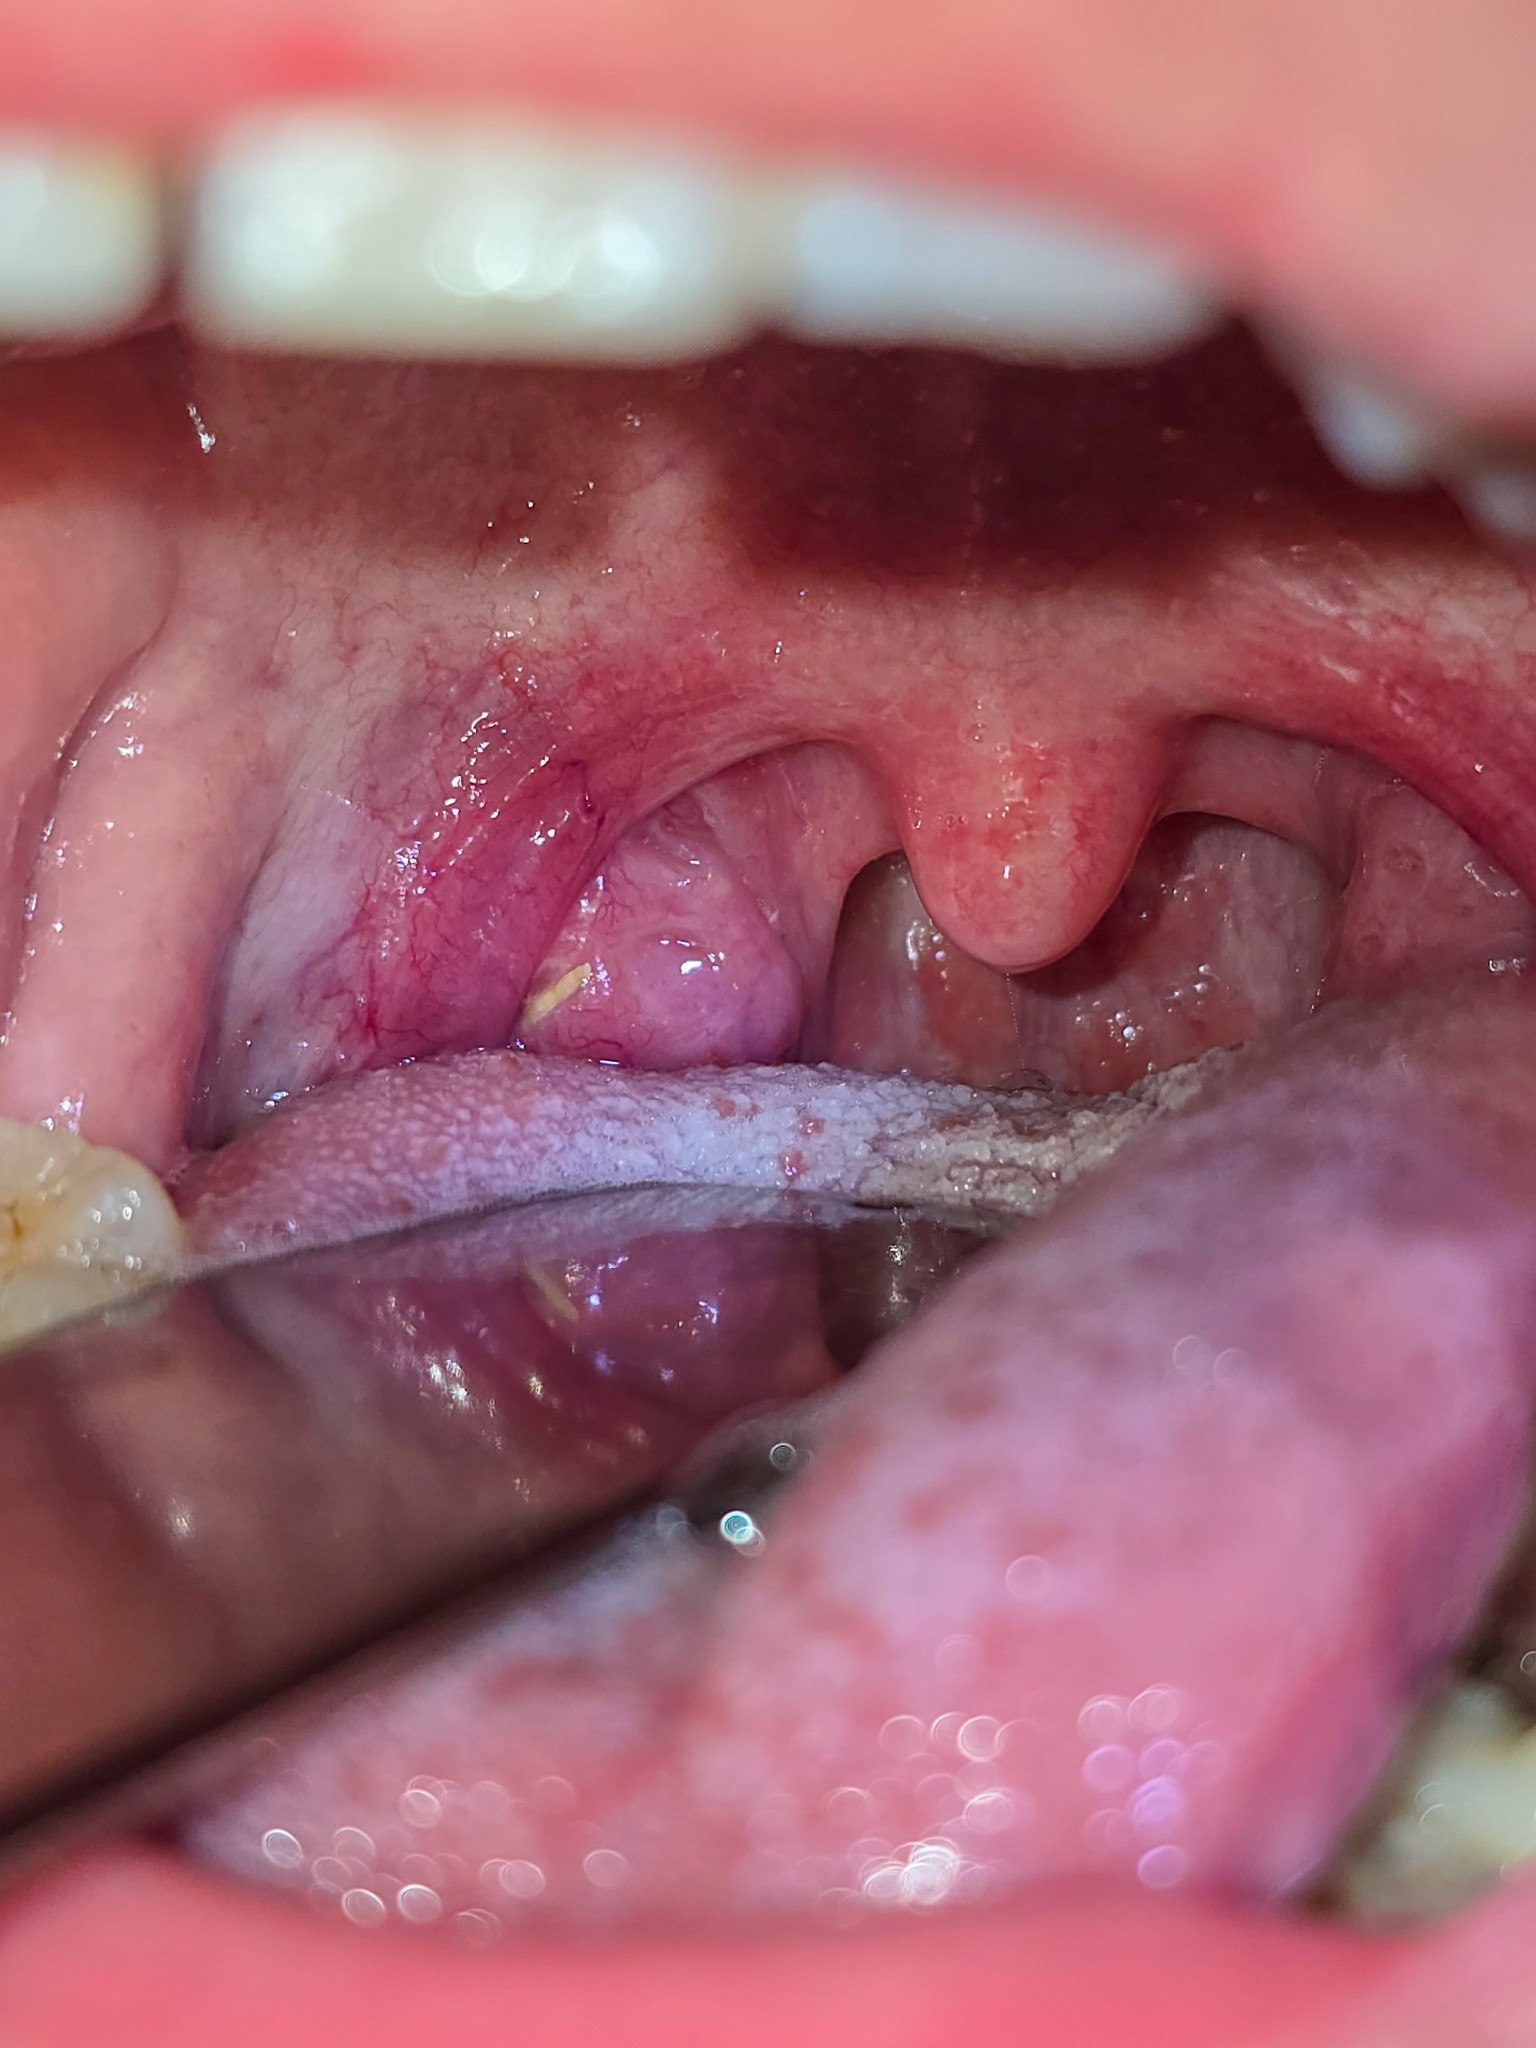

แต่พอคนไข้อ้าปากปุ๊บ... ชัดเลยครับ! 😱

น้องก้างปลาพุ่งทิ่มตาหมอเลย (เปรียบเทียบนะครับว่าเห็นชัดมาก) มันปักคาอยู่ที่ต่อมทอนซิลด้านขวาพอดีเป๊ะ จังหวะนรกจริงๆ ครับ

ผมเลยจัดการใช้อุปกรณ์คีบออกมาให้ คนไข้บอกว่า "หายปวดเป็นปลิดทิ้ง!" เหมือนยกภูเขาออกจากอกเลยครับ